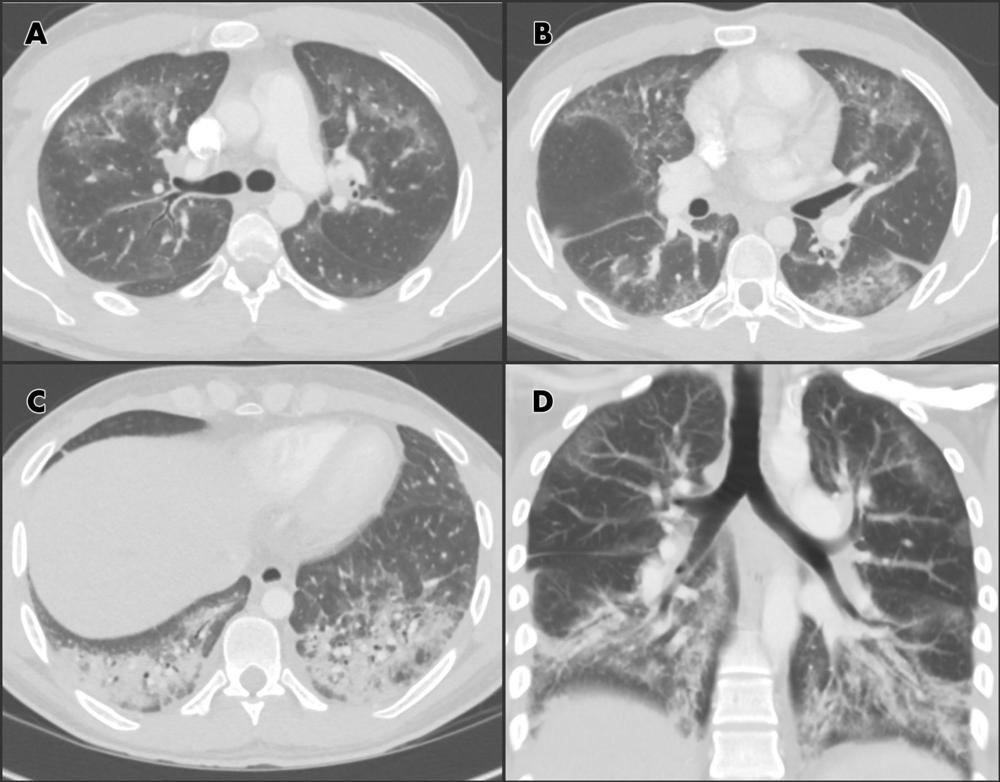

Figure 8 (from Radiology: Cardiothoracic Imaging). Chest CT angiographic images in a 24-year-old man with a history of e-cigarette use. A–C, Selected axial sections of the lung presented on lung windows reveal patchy ground-glass opacities distributed bilaterally with some, A, B, subpleural sparing and, C, consolidation in the lung bases. D, Coronal oblique thick-slab average intensity reconstruction shows the predominance of the findings in the basal lungs and demonstrates the peripheral subpleural sparing.